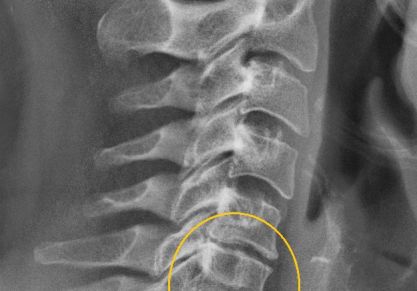

Таблетки от шейного, грудного и поясничного остеохондроза: рейтинг популярных

Какие таблетки принимать при остеохондрозе шейного, грудного и поясничного отдела. Названия препаратов, описание воздействия и противопоказания.